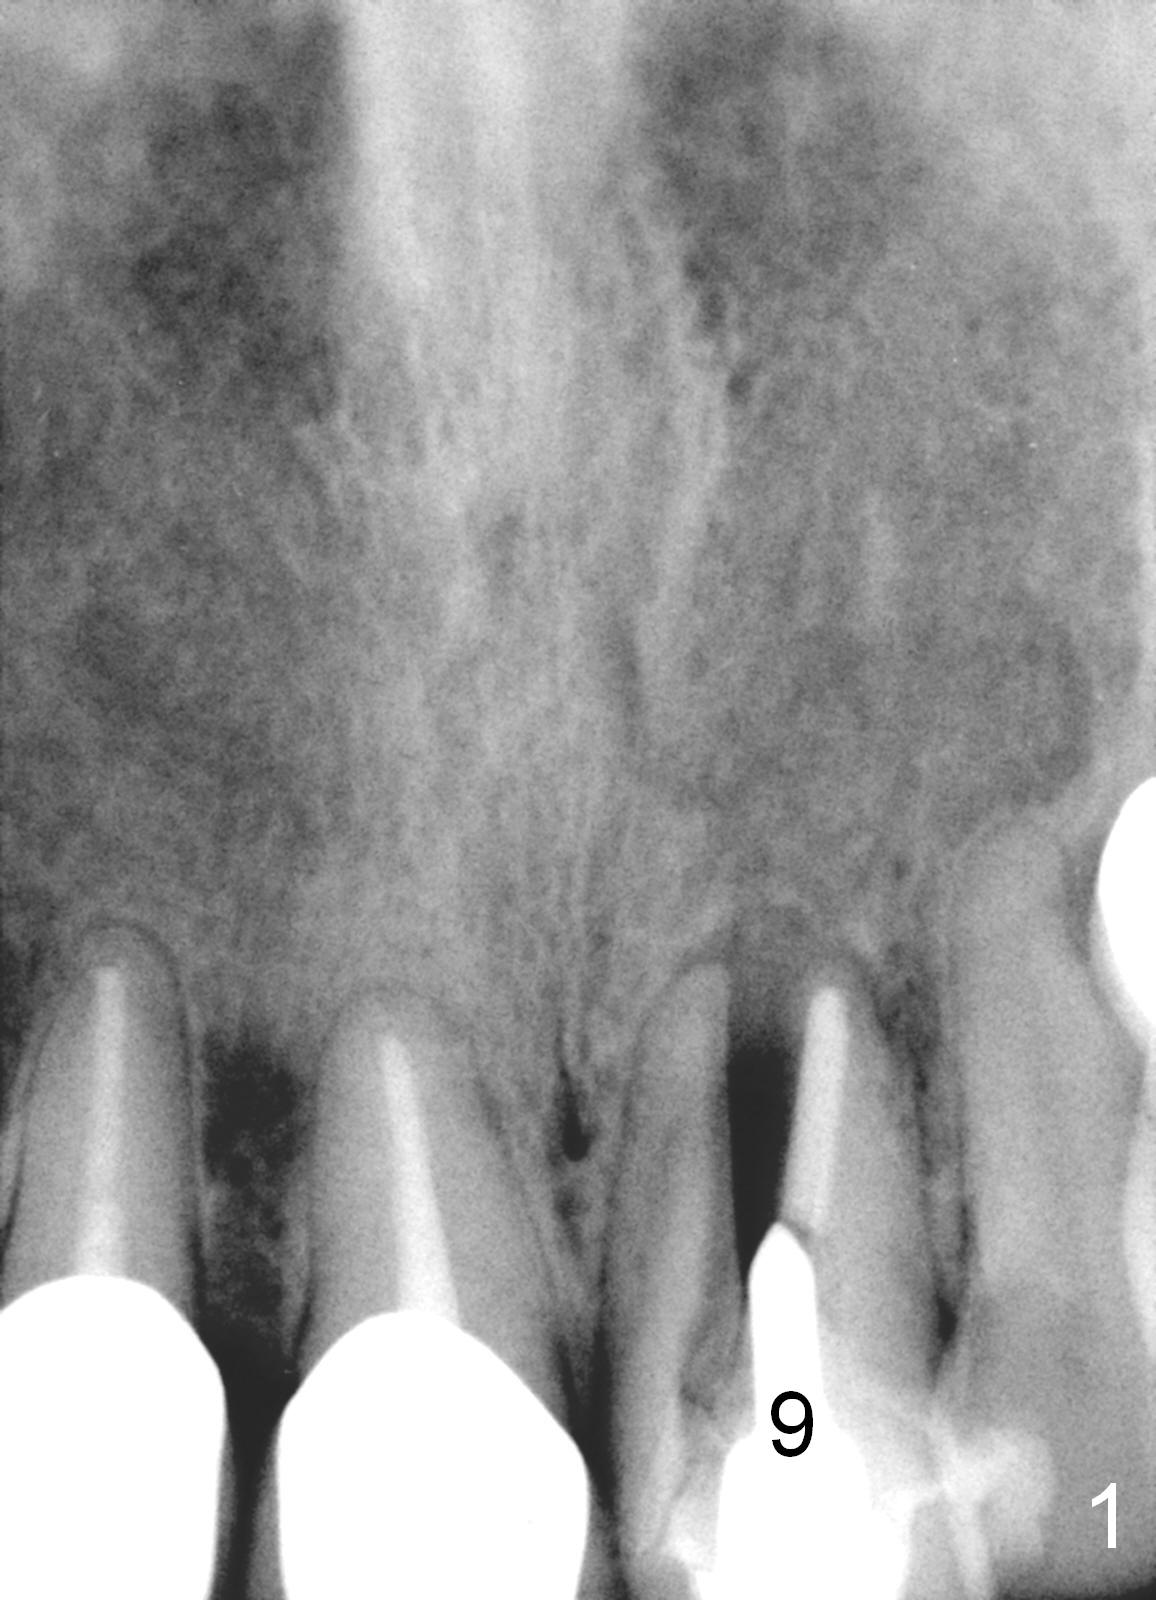

A 64-year-old woman (XP) has multiple restoration, requesting implant replacement for the loose upper left central incisor (Fig.1).  It is asymptomatic, although there is labial swelling with purulent discharge from the labial gingival sulcus.  The labial plate must have been absent.  After granulation tissue removal and socket treatment with no antibiotic, place a 4x16 mm implant in a correct position (Fig.2).  Place Osteogen tape against the labial defect and then bone graft with a small piece of gauze in the implant well.  Since the lady is small in stature with possible osteoporosis and X-ray is particularly dark (Fig.2 (Fig.1 has been lightened in brightness)), use low voltage when taking new X-ray.  Take preop photos to show labial swelling and purulent discharge from the labial gingival sulcus.